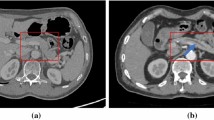

CPR images were obtained based on the pancreatic phase images, which were obtained 20 s following the first scan. Manually created CPR images were generated by one of 10 radiology technicians from our institution who were experienced in the task (at least 30 cases). Images were generated on the operator console of the CT system. They traced the pancreatic duct centerline in the axial image, reconstructed it, and finally generated a single CPR image along the MPD (Fig. 2).

Generation of automatic CPR images

The automatic CPR images were created using software under development (Fig. 3), which encompasses three processes: pancreas segmentation, pancreatic duct segmentation, and pancreatic duct centerline detection.